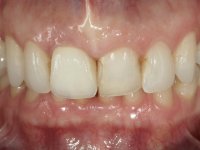

After the impression of the implant using a double-mix technique with double viscosity and the collection of shape and color information by the ceramist, we proceed with the work. In the model, a syn octa was placed over the implant, and a screw was placed on it to assess its emergence in relation to the incisal edge. Then, an adequate emergence profile in the artificial gingiva was prepared. A abutment with characteristics suitable for overbite and simultaneously capable of receiving a veneer was waxed on top of this scenario. This waxing gave rise to the manual milling of a very personalized abutment. An infrastructure in Zr was also made for the veneer with a very great adaptation to the abutment. On this infrastructure ceramics were placed. Ceramic fluorescence sought to compensate for the lack of fluorescence that Zr had and obviously further customize the aesthetics. The adhesive bridge was removed and the definitive work was placed. The syn octa was initially tightened with 35 N to the implant and then the Zr abutment was tightened over the syn octa with 15 N. The access hole was plugged and then the veneer was cemented with resin-reinforced glass ionomer. After 15 years, the patient returned to the consultation with tooth mobility. Fortunately, nowadays we have the possibility of having dynamic tightening wrenches that allow tightening screws with greater inclinations. An access cavity was made without damaging the incisal edge of the veneer. Tightening was done with a dynamic wrench with 15 N torque. The hole was covered with Teflon and filled with composite resin. This solution allowed the problem to be solved in a simple and economical way.